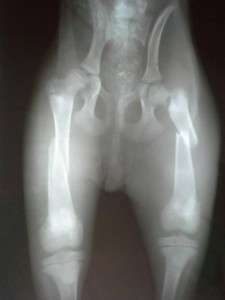

He was living his life in a market, where people threw him a bit of bread at times. At night, he took shelter under the market stands, or under a car parked in the market place. Yet, everything turned into a nightmare, when a car backed up and the poor dog couldn’t get out of the way. He was left there unable to move, while the heartless person who hit him abandoned him and went on with his life. A desperate call from a lady who worked at the market drew our attention, and we could not ignore the situation, although we are swamped with animals and problems of all kinds. The little dog’s first surgery was successful, and now he is at the clinic, where he will have to undergo more surgery. We hope that in the end he will walk again.

Hit by a car